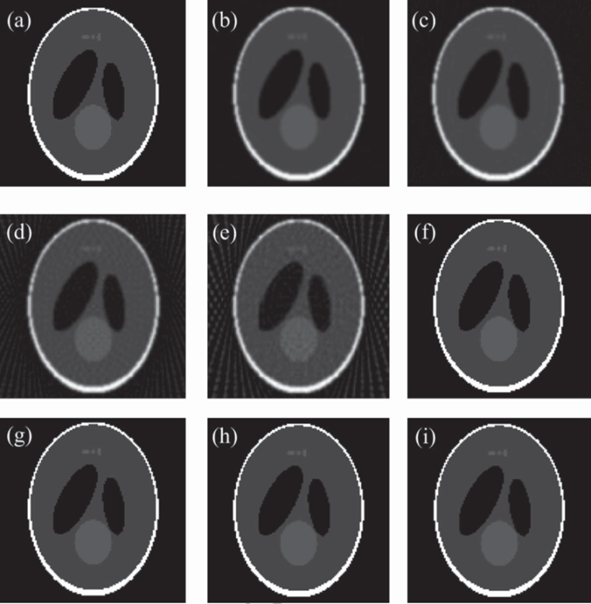

实验结果表明:与解析重建算法FDK相比,提出的算法在投影数较少的情况下,仍能获得较好的重建图像质量(见图1);与两种现有的基于TV正则化的迭代重建算法(ASD-POCS,EM-TV)相比,所提算法收敛速度提高6倍以上,且表现出更强的图像去噪和边缘保持能力(见图2)。此外,采用GPU加速手段使得上述迭代算法的重建时间大为减少(见表1)。

图1. 解析算法与3DA-TVAL3算法的重建结果。(a)Sheep-Logan体模的原图像;(b-e)360,180,90,60个投影角情况下,解析算法FDK的重建结果;(f-i)360,180,90,60个投影角情况下,3DA-TVAL3算法的重建结果。